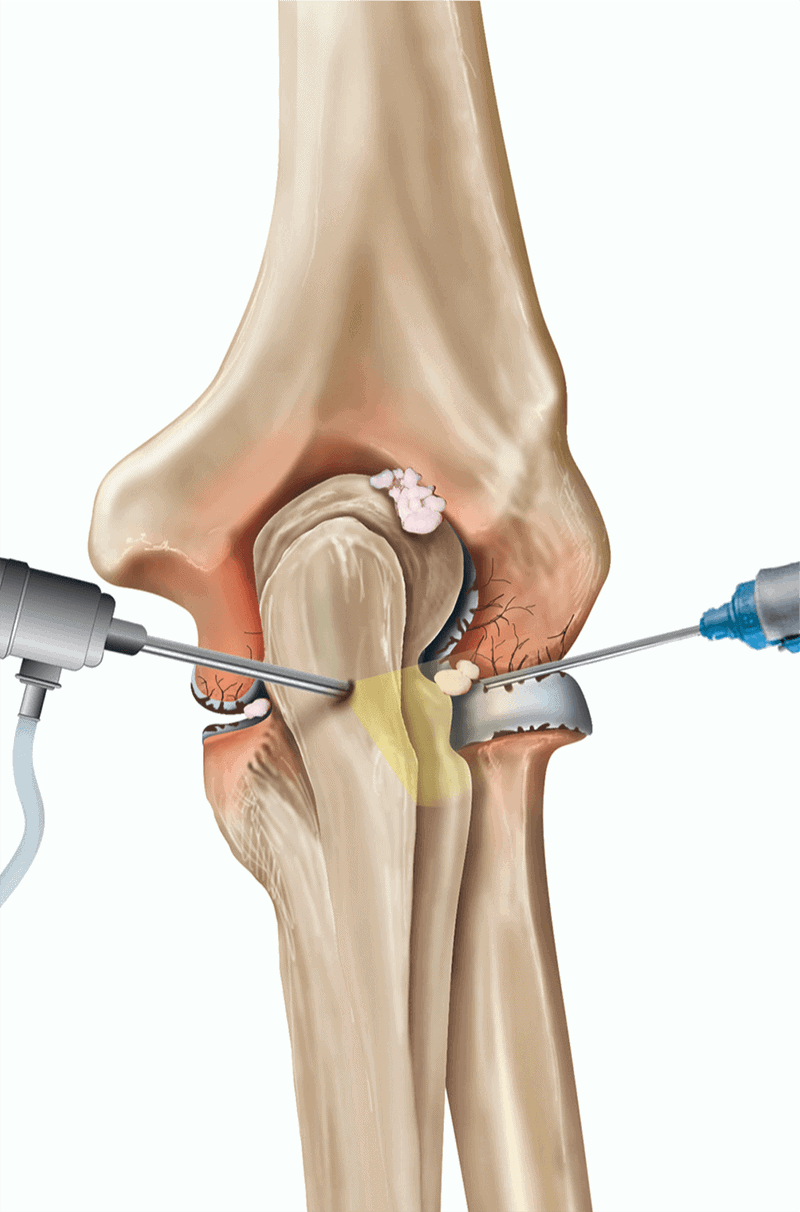

Elbow arthroscopy is performed using an arthroscope—a pencil-thin instrument with a camera and light—inserted into the joint. This allows the surgeon to see the inside of the elbow and guide small surgical tools through additional tiny incisions to perform repairs.

| · Loose bodies (cartilage or bone fragments) – Removal to improve motion and reduce pain | |

| · Osteoarthritis or post-traumatic arthritis – Debridement (removal of bone spurs and damaged tissue) | |

| · Osteochondritis dissecans – Debridement or microfracture technique | |